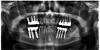

alex75 Опубликовано 9 октября, 2013 Поделиться Опубликовано 9 октября, 2013 Вот одна из первых работ 10-летней давности Ссылка на комментарий

alex75 Опубликовано 24 октября, 2013 Поделиться Опубликовано 24 октября, 2013 Это радикс. Там был открытый синус с двух сторон+имплантация и неудачная попытка ветикальной аугментации с одномоментной постановкой имплантов. Ссылка на комментарий